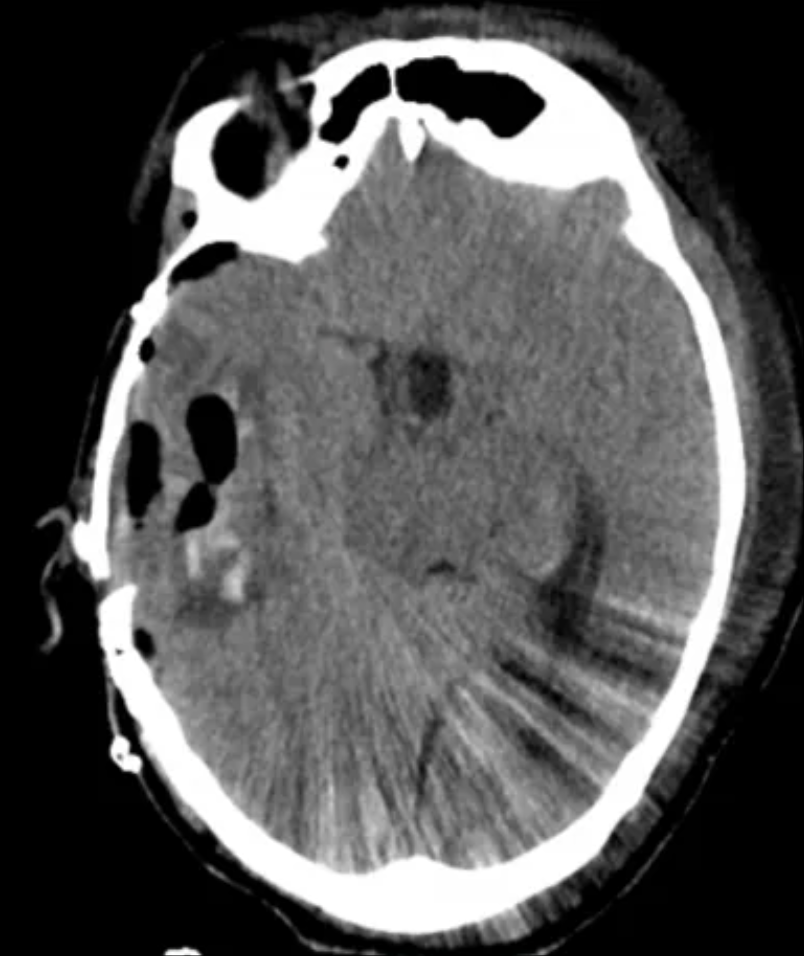

今年6月,扎西在外院检查后发现,其颅底颈静脉孔区存在巨大颅内外沟通肿瘤,这个肿瘤正是导致他十多年来所有症状的根源。

巨大颅内外沟通肿瘤暗藏杀机

处理颈静脉孔巨大颅内外沟通肿瘤,远不止是“棘手”二字可以概括,它是神经外科领域公认的顶尖挑战之一。扎西此前多方辗转求医,得到的多半是无奈地摇头。

上海冬雷脑科医院脑血管专家盖延廷主任介绍:“颈静脉孔是颅底的一个骨性孔道,像一条至关重要的‘电缆管道’,里面有负责大脑血液回流的颈内静脉、负责大脑供血的颈内动脉等关键‘电缆’通过。

此例颈静脉孔巨大颅内外沟通肿瘤具有三重高危特性

一是贯穿颅内外,经颈静脉孔同时侵犯颅内和颈部,手术需要同时打开颅腔和颈部,解剖结构更复杂;

二是肿瘤血供异常丰富,10多根血管深入瘤体缠结,手术中将出血凶猛;

三是肿瘤区域与颈静脉孔中的‘电缆’、脑干紧密粘连,稍有不慎将导致神经受损,甚至呼吸心跳骤停。”